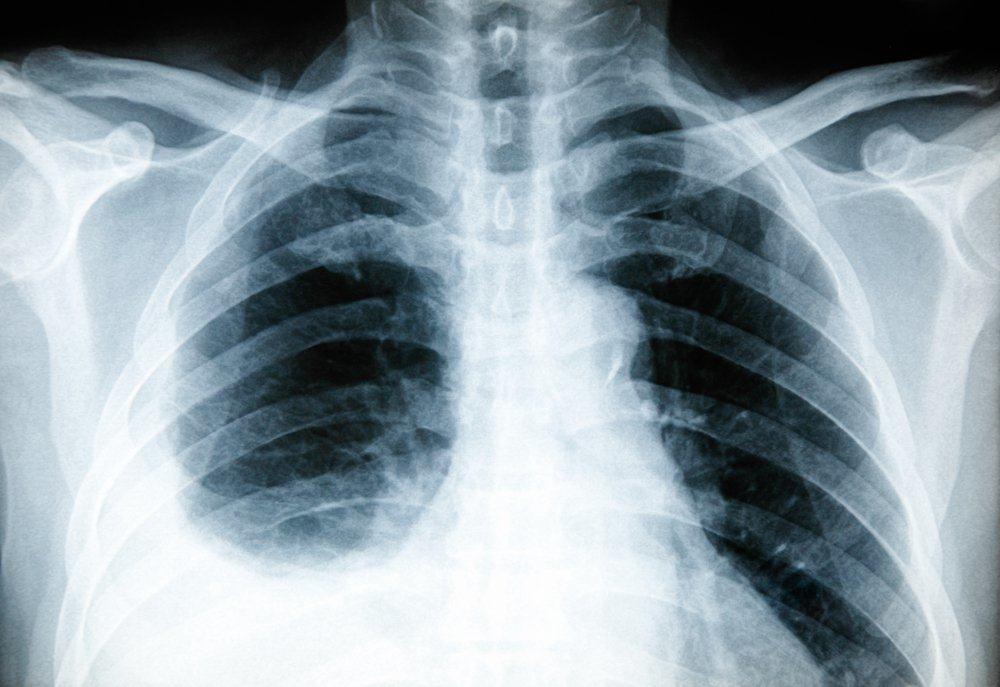

1. X-ray dada

Tes x-ray di bagian dada dapat membantu dokter mengetahui adanya peradangan pada paru-paru Anda. Jenis x-ray yang dilakukan adalah dekubitus, yaitu x-ray yang diambil ketika Anda berbaring dengan posisi miring.

Dengan posisi ini, penumpukan cairan yang terdapat di pleura Anda dapat terlihat secara lebih jelas.